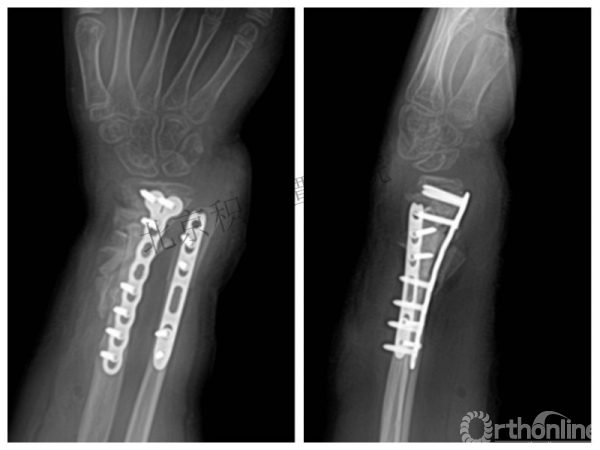

病例分享四

女孩、8岁,桡骨远端骨折

原始损伤

伤后1个月

伤后14个月